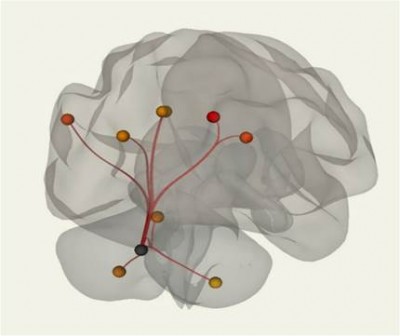

- Разработка инновационных технологий исследования нейронных сетей головного мозга и искусственного интеллекта.

«Изменения коннектома головного мозга у пациентов с детским церебральным параличом в поздней резидуальной стадии при транслингвальной нейростимуляции». Обобщена МР-семиотика структурных и функциональных изменений головного мозга у детей со спастической диплегией. У детей с ДЦП в поздней резидуальной стадии преобладает снижение коннективности между компонентами сети выявления значимости и корой лобно-теменной области, компоненты которой также структурно связаны с компонентами сенсомоторной сети. При выполнении коннектометрического анализа трактов после ТЛНС (основная группа) выявлено повышение фракционной анизотропии более чем на 20 % (p < 0,001) в передней спайке (47 % от общего количества волокон), правом нижнем лобно-затылочном пучке (13 % волокон), левой поясной извилине (10 % волокон), правой зрительной лучистости (6,7 % волокон), мозолистом теле (6 % волокон), правой поясной извилине (1,3 %) (рисунок).

При выполнении коннектометрического анализа трактов после стандартной двигательной реабилитации (группа сравнении) статистически значимого повышения фракционной анизотропии (более чем на 20 %) не выявлено. При проведении диффузионной МРТ у детей с ДЦП в поздней резидуальной стадии выявлено статистически значимое снижение фракционной анизотропии в трактах белого вещества головного мозга, что свидетельствует о нарушении общих процессов миелинизации и, следовательно, скорости проведения нервных импульсов по их аксонам. Выявлены структурные и функциональные изменения головного мозга у пациентов с ДЦП после ТЛНС, которые свидетельствуют об усилении активации процессов нейропластичности.

Результаты: Получены данные об изменении морфометрических данных у пациентов с прогрессирующим типом течения рассеянного склероза в виде снижения объема белого вещества головного мозга, а также белого вещества мозжечка относительно возрастной нормы, с компенсаторным увеличением объема ликворных пространств по конвекситальной поверхности, увеличением объема III и боковых желудочков (в cм3/%). Также отмечалось снижение абсолютного объема субкортикальных структур (таламус, бледный шар, диэнцефалон) относительно возрастной нормы.

Получены данные о наличии изменений с сети пассивного режима головного мозга при помощи использовании методики функциональной МРТ в покое. Наиболее выраженные изменения отмечаются в функциональной коннективности медиальной префронтальной коры (МПФК), которая играет важную роль в передаче соматосенсорной информации структурам, которые отвечают за моторные и висцеральные реакции, участвуют во внутренней системе вознаграждения и отвечают за принятие решений. Отмечается снижение функциональной коннективности между МПФК и правой дорсальной сетью внимания, правой супрамаргинальной извилиной, а также наблюдалось усиление функциональной связи с задней поясной извилиной, парацингулярной извилиной с обеих сторон, правой латеральной теменной корой, субкаллозальной корой, задней поясной корой, корой предклинья и правой супрамаргинальной извилиной. Отмечается латерализация изменений функциональной связности (преимущественно справа).

3. Научные исследования структурно-функционального состояния головного мозга при различных неопухолевых и опухолевых заболеваниях.

Для этого применяется методика функциональной МРТ в покое и сложные постпроцессорные алгоритмы построения карт коннективности головного мозга.

Работы ведутся совместно с учеными НИО неврологии и нейрохирургии Центра, а также специалистами других организаций города и страны.

| Коннектом головного мозга. Мозжечковая рабочая сеть покоя. | Статистическая обработка данных толщины коры головного мозга пациентов при рассеянном склерозе. |